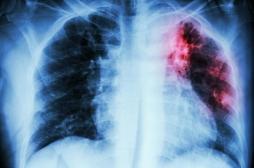

maladie infectieuse

LES MALADIES